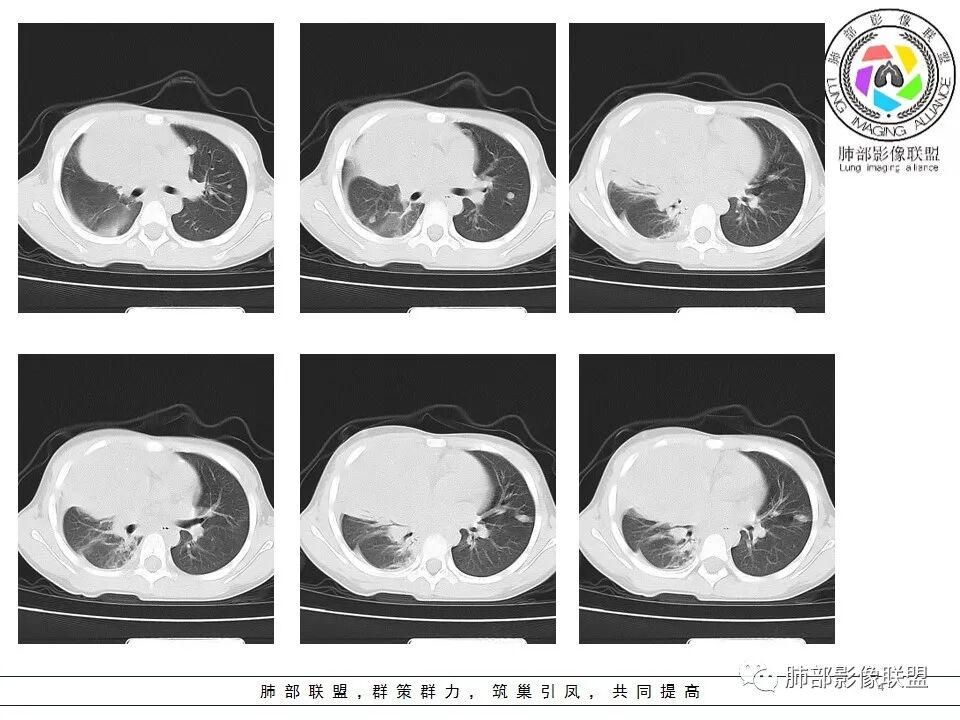

右前纵隔巨大软组织肿块,主要偏向右侧生长,边界不清,密度不均匀,内见大片状低密度坏死区及散在钙化灶,未见骨骼影及脂肪密度影。、双肺随机分布的转移瘤结节,右肺肺不张及右侧胸腔积液,提示恶性肿瘤病变伴双肺及胸膜转移。

前纵隔肿块常见的良性病变为畸胎瘤,恶性肿瘤有侵袭性胸腺瘤或胸腺癌、淋巴瘤、恶性生殖源性肿瘤、Askin(Pnet)瘤等。患儿9岁,30岁以下的胸腺肿瘤非常罕见。而且从病变密度不均,缺乏多结节堆积感,可见钙化等淋巴瘤的可能性不大。虽然这个病例缺乏增强及相关实验室检查,小儿前纵隔恶性肿瘤中恶性生殖细胞肿瘤相对常见,须鉴别的是Askin(Pnet)瘤,可结合有关HCG,AFP和LDH实验室检查帮助甄别。

精原细胞瘤

临床缺乏特异性,几乎见于男性,一般血清LDH升高,部分β-HCG轻度升高,精原细胞瘤不产生AFP,血AFP升高可考虑非精原细胞瘤或混合生殖细胞肿瘤。影像表现一般肿块巨大,分叶状,边界不清,可浸润性生长,无钙化及脂肪,有纤维分隔,轻中度强化,易转移。

男性,32岁,精原细胞瘤

畸胎瘤

前纵隔最常见的生殖细胞肿瘤,分为良性的成熟畸胎瘤和恶性的未成熟畸胎瘤;良性畸胎瘤肿瘤标志物一般为阴性,恶性畸胎瘤特别含有胚胎成份的畸胎瘤部分肿瘤标志物可以阳性,如何AFP、HCG、LDH或CA199。成熟畸胎瘤影像上一般为多房囊性肿瘤,大部分含有脂肪密度和钙化,可发生破裂;而不成熟畸胎瘤肿块边界不清楚,包膜不完整,对周围结构有压迫或侵犯,可以钙化及脂肪密度,还有不均质强化或见血管影均可提示未成熟畸胎瘤。